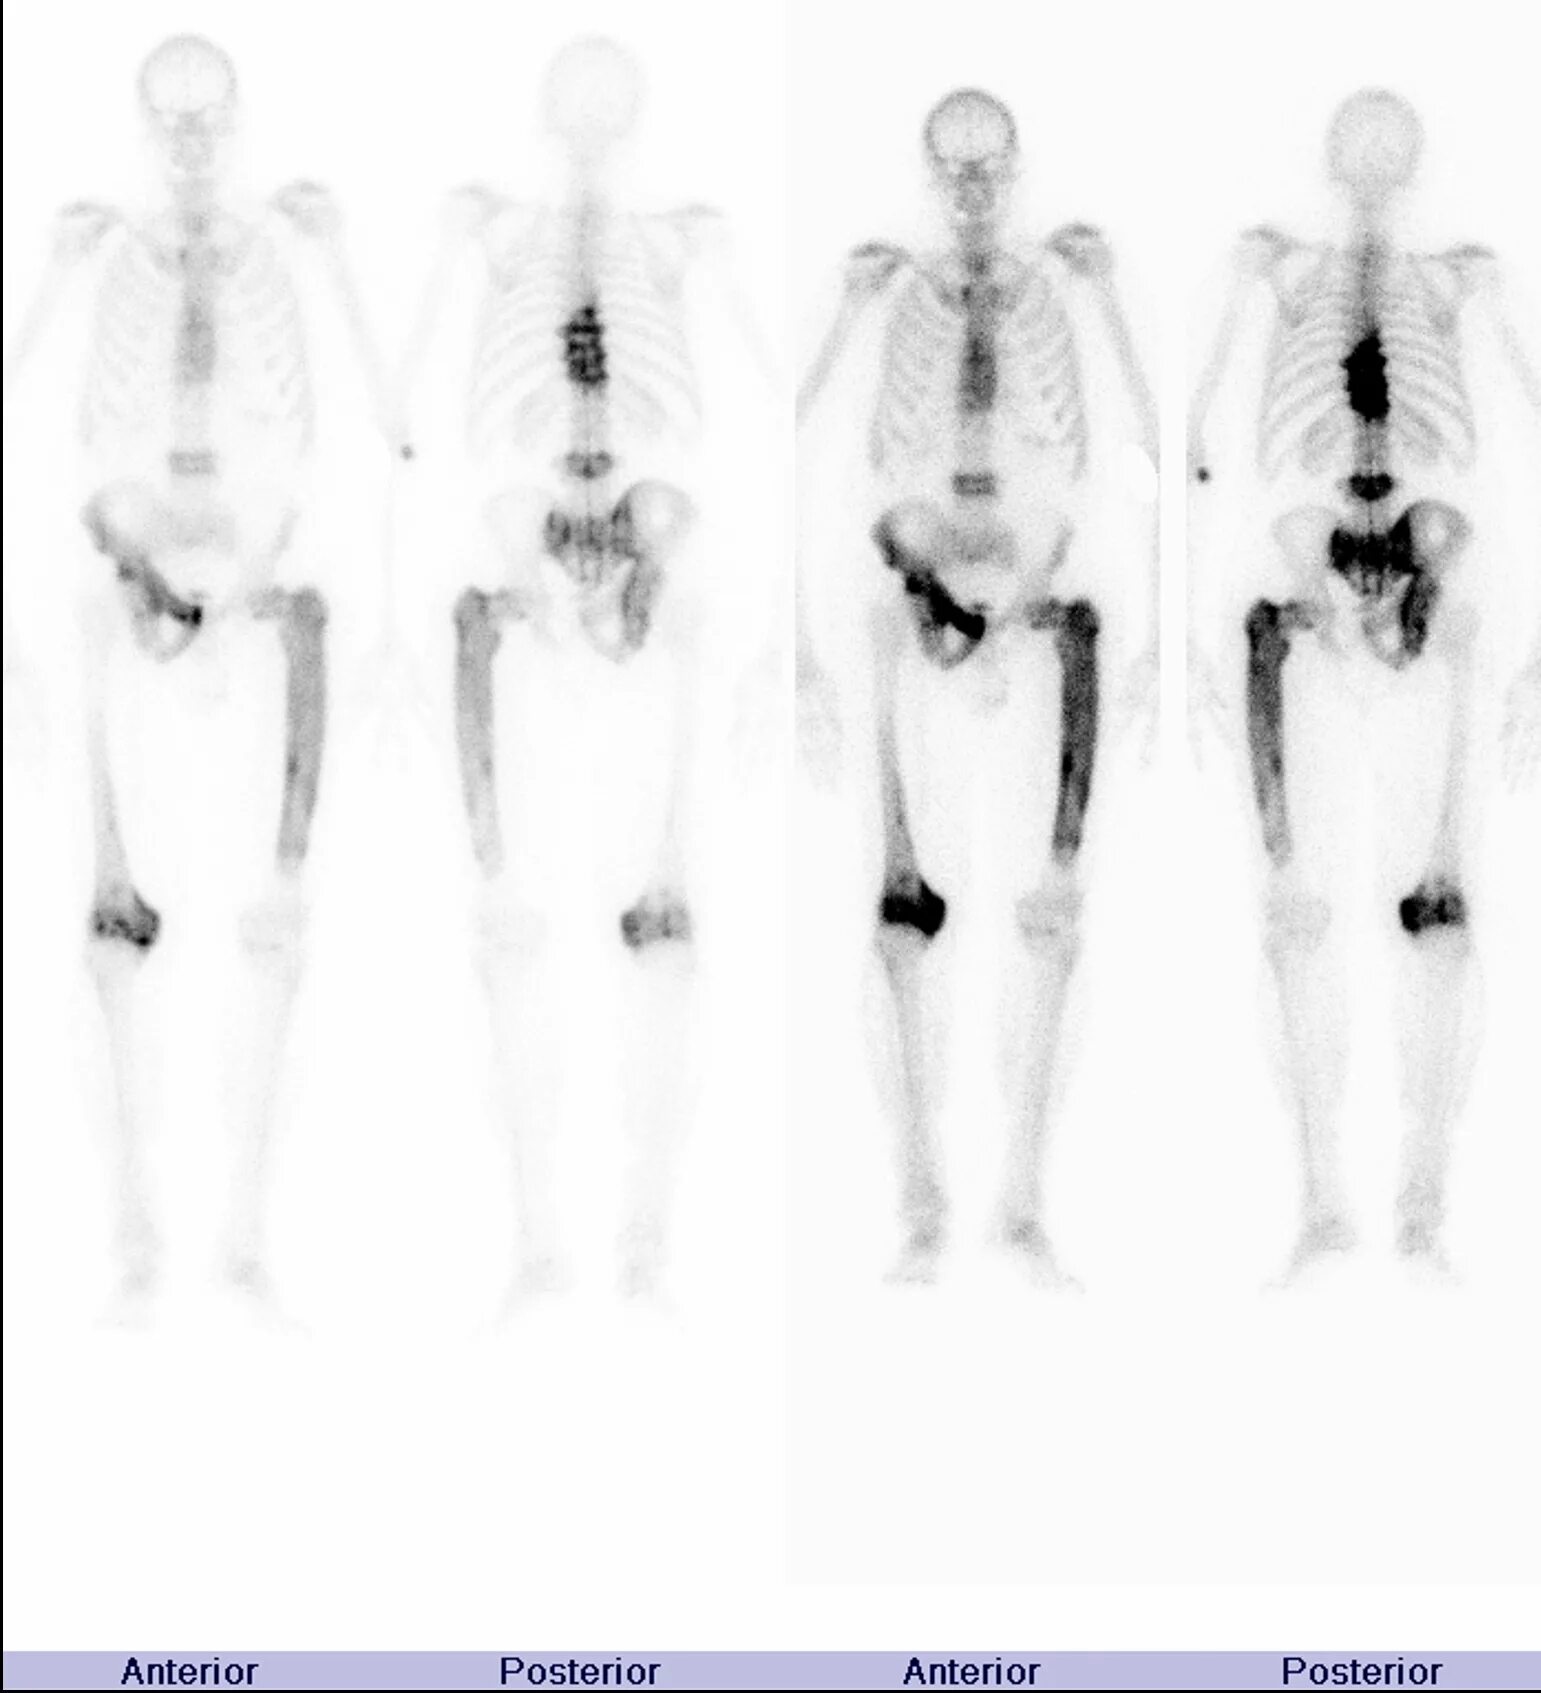

Метастазы костей можно вылечить